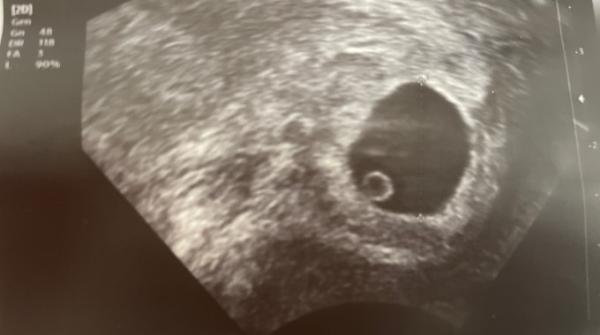

Hallo zusammen, ich bin total verzweifelt.. ich hatte am 22.12 einen Termin beim Frauenarzt und man sah nur eine Fruchthöhle mit einem weißen Mini Punkt.. eine Woche später sieht man eine Fruchthöhle mit einem Dottersack (Siehe Bild) Laut Ärztin Ssw 7 (6+6). Man sieht keinen Embryo und sie sagte, dass eventuell eine Ausschubung gemacht werden soll, wenn es bald nicht blutet. Aber es gibt doch auch Eckenhocker richtig? Wie war es bei euch? Sieht die SS laut dem Bild intakt aus? Ein dottersack ist ja vorhanden. Bitte um Rückmeldung ich verzweifelt. Danke Mein HCG wert liegt nun bei fast 45.000

Bild zu 7 Ssw - Schwanger - wer noch? Rund um die Schwangerschaft

Und wieso bitte? Also ne Eileiterschwangerschaft kanns ja auch nicht sein und ein Windei ist es ja auch nicht, sonst würde es bei beidem ja keinen Dottersack geben. Und wieso steigt das HCG? Meistens sehen die Fruchthöhlen dann auch deformiert aus, deine sieht normal aus.